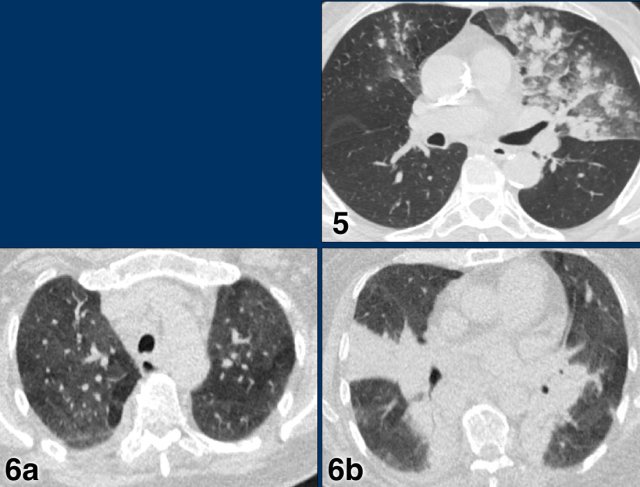

Examples of CO-RADS 3. Click to enlarge. Examples of CO-RADS 3. Click to enlarge.

Case 5

7 day of complaints.

CT: multifocal consolidations with surrounding GGO.

PCR negative.

Case 6

Recent Influenza A . History of pulmonary hypertension.

Started coughing again.

CT: bilateral central consolidations with diffuse GGO.

Re-test: COVID-19 PCR: negative and Influenza A: positive.